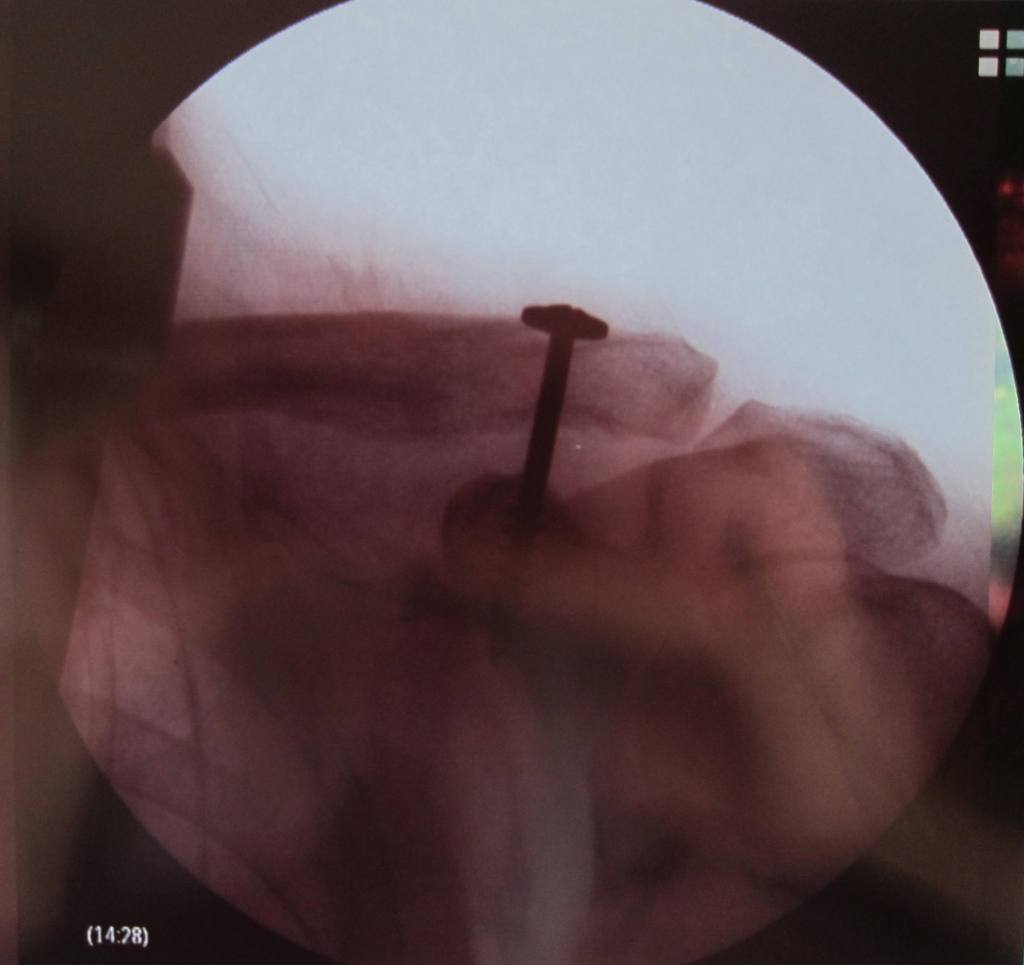

Screw is out. Fuzzy head is clearing. Ah, to have range of motion again, what a treat. Doc says, “Take it easy for the first few days, and no contact sports for 3 months’. Like I haven’t been taking it easy for years and the last ‘contact’ sport I played was air hockey at that bar in Mt. View (still table Champion!). Unless you count getting hit by your own golf ball off a tree ricochet a contact sport? Whatever.

Here’s the $385 dollar screw in question –

Yes, it’s a Phillips head. No, he didn’t use an electric screwdriver. Yes, I’m going to make a keyring out of it. And yes, it really cost 385 bucks – Wanna know why your healthcare insurance is so expensive?